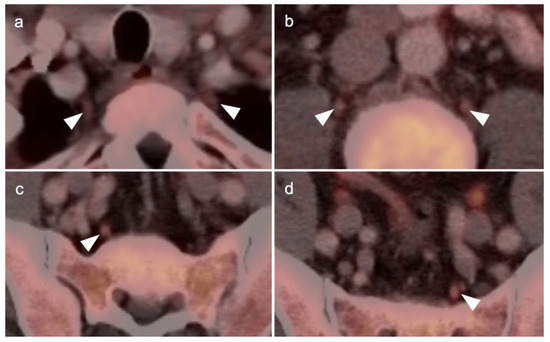

2.4. Cervical Cancer

2.6. Vulvar Carcinoma